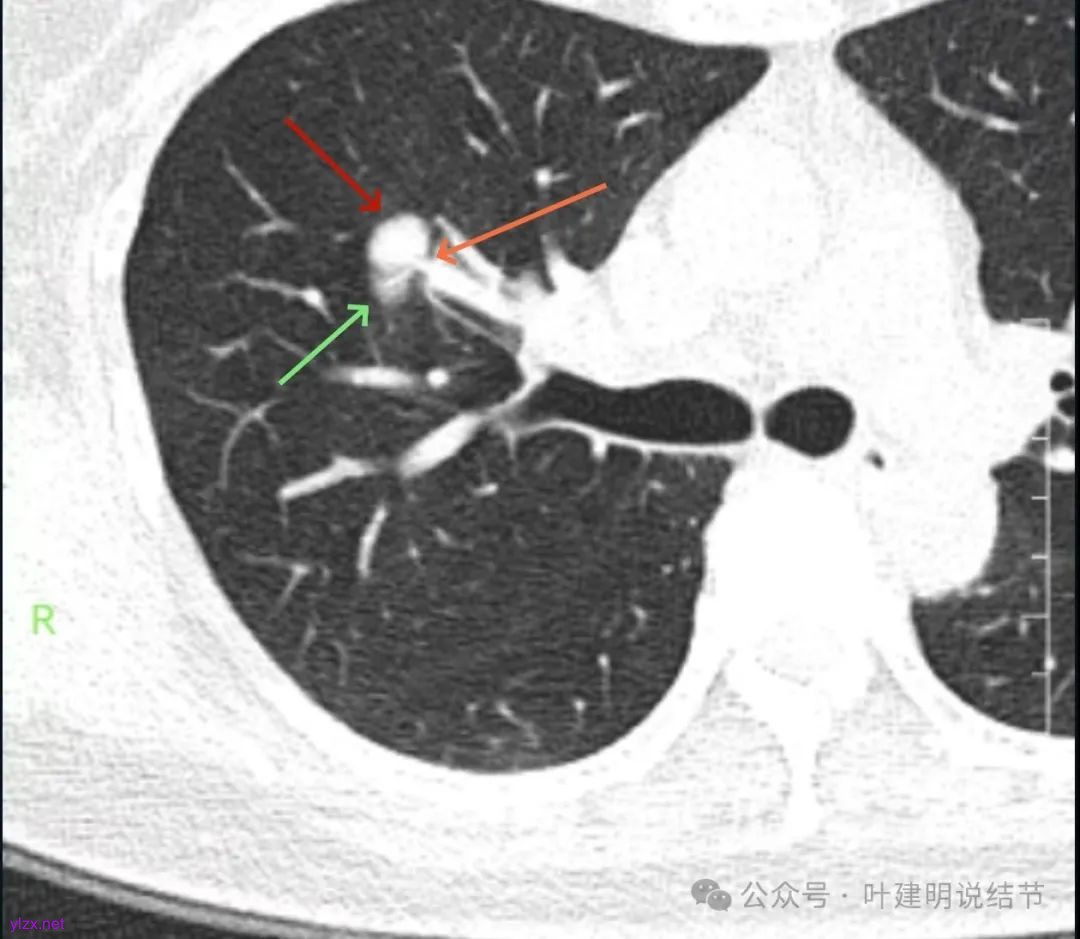

你的右上叶这个病灶基本上肯定是肺癌,要尽快处理。从影像上看有以下特点:1、整体轮廓清楚,不似普通炎症的周围有晕或阻塞性改变;2、边缘明显的浅分叶,总体上的感觉膨胀性明显,不管哪个层面看上去都是鼓鼓的;3、边缘区域有磨玻璃成分而且也是分叶状的;4、部分层面见血管进入;5、空腔病灶的壁厚薄不均,内壁不光滑。我考虑中低分化肺癌,由于腔静脉旁有明显肿大淋巴结,需要进一步完善增强CT以及PET-CT检查以明确有无远处转移,是否仍可手术治疗(从病灶本身来说是可以肺叶切除治疗的)。要尽快处理。意见供参考!